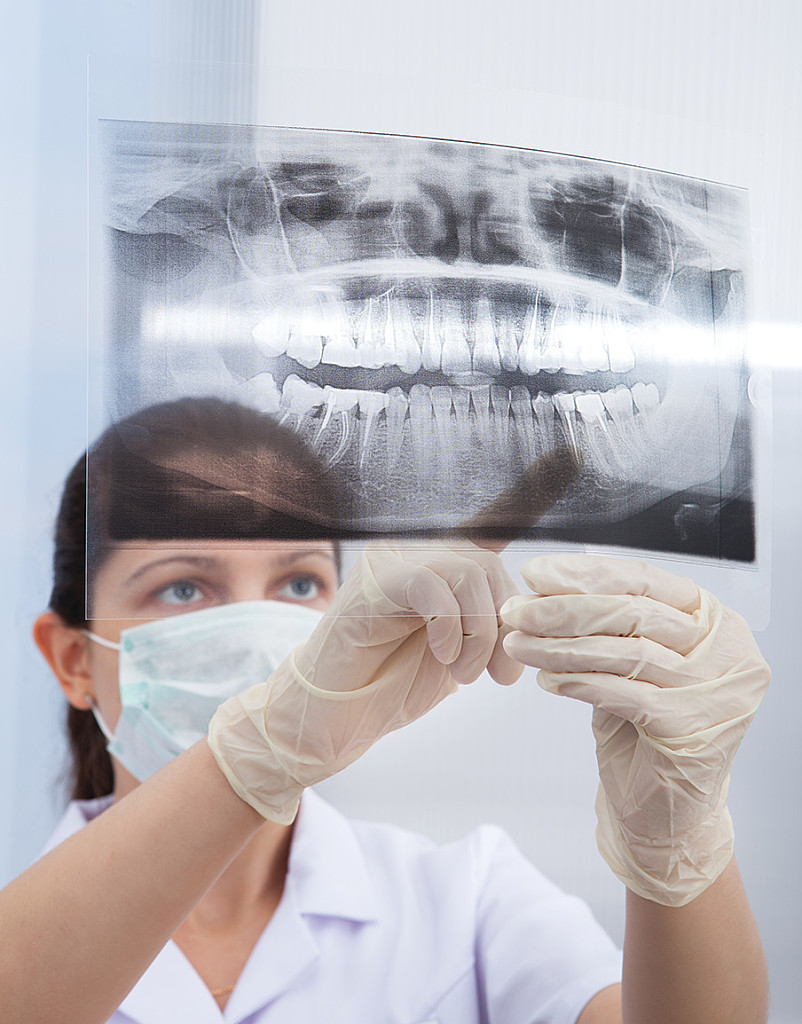

A new paper in Science Advances describes for the first time how minerals come together at the molecular level to form bones and other hard tissues, like teeth and enamel.

The University of Illinois Chicago researchers who published the paper described their experiments -- which captured high-resolution, real-time images of the mineralization process in an artificial saliva model -- and their discovery of distinct pathways that support bone and teeth formation, or biomineralization.

To capture the images, the researchers used a unique micro-device that made it possible to use electron microscopy with a liquid model. Using this method, the researchers were able to monitor chemical reactions in the model on the smallest scale.